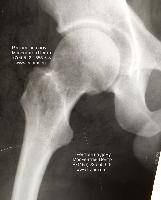

В случае перелома шейки бедра компания МосРентген Центр госпитализирует в Склиф для эндопротезирования.